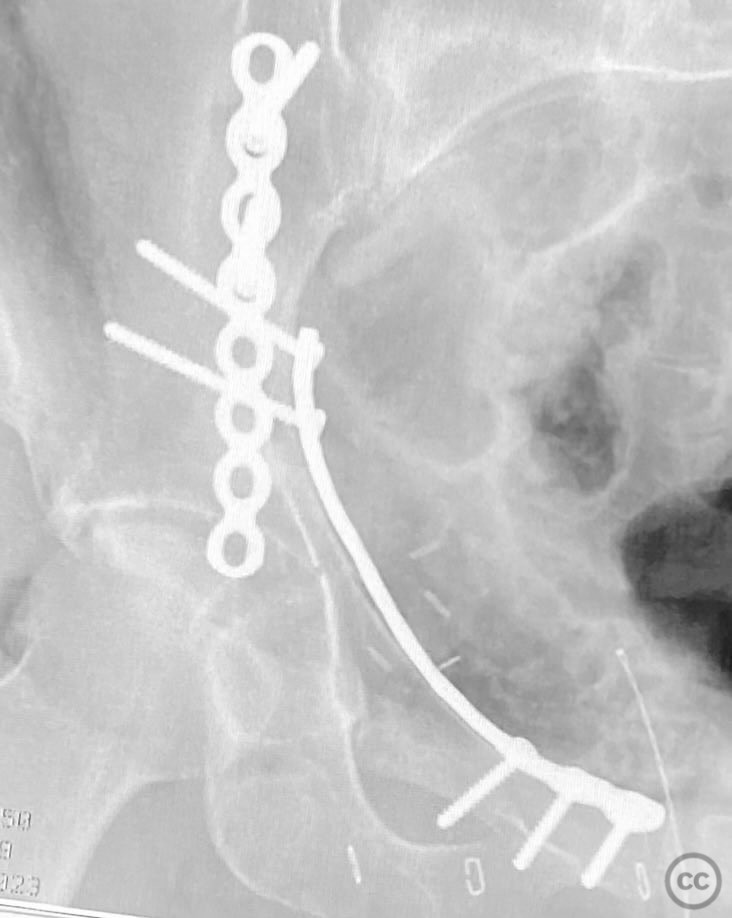

Clinical and radiological findings:  The patient sustained an acetabular fracture with a rare posterior medial dome impaction fragment, as demonstrated on AP pelvic radiographs obtained in skeletal traction. Surface renderings and axial CT images revealed multiple incomplete fracture lines, including a rhomboid-shaped cortical fragment adjacent and proximal to the anterior column/wall fragment. Coronal and sagittal reconstructions further delineated the impacted articular fragment and its relationship to the surrounding acetabular dome. The fracture pattern is classified as AO/OTA 62B3 (associated both-column fracture with dome impaction).

Planning remarks:  The preoperative plan involved an ilioinguinal approach to the acetabulum, utilizing the intrapelvic interval for initial reduction and stabilization of the posterior column with a contoured intrapelvic plate. Sequential reduction of the anterior column and direct management of the impacted dome fragment were planned, facilitated by temporary removal of the rhomboid cortical fragment.

Anatomical surgical approach:  A classical ilioinguinal approach was performed, developing the lateral, middle, and medial windows. The intrapelvic interval was used to access the quadrilateral surface and posterior column. The rhomboid cortical fragment was excised to allow direct visualization and manipulation of the impacted posterior medial dome fragment. Reduction was achieved using a spiked pusher under fluoroscopic guidance. The defect was filled with morselized allograft, and the rhomboid fragment was anatomically reduced. The anterior column was stabilized with a contoured plate. Posterior column reduction was further improved using a reduction clamp applied with one tine lateral to the anterior inferior iliac spine (AIIS) and the other on the quadrilateral surface via the middle window, followed by lag screw fixation.